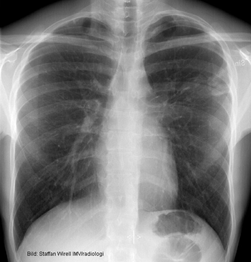

Lungröntgen av hostande patient:

Tuberkulos

Vad visar bilden?